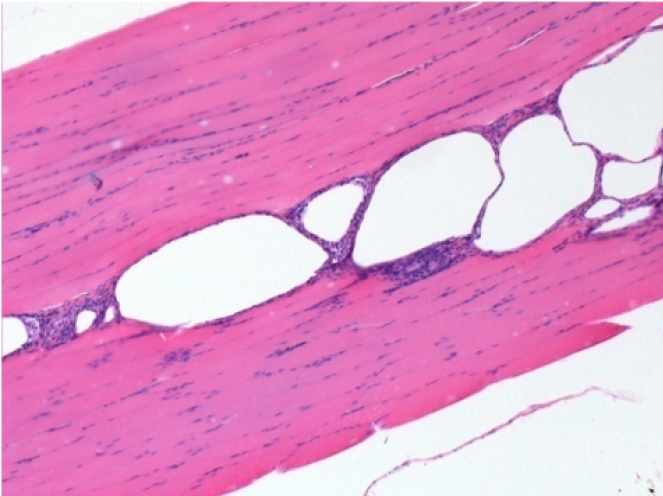

Через 1 місяць після ін'єкції Ендопілу 0,1 мл у правий претибіальний м'яз.

Те, що видно на знімках чорним кольором, не є некрозом, як можуть собі уявити деякі науковці!

Насправді, слід взяти до уваги 4 висновки